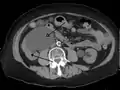

The choice of imaging depends on the clinical presentation (history, symptoms and examination findings). In the case of renal colic (one sided loin pain usually accompanied by a trace of blood in the urine) the initial investigation is usually a spiral or helical CT scan. This has the advantage of showing whether there is any obstruction of flow of urine causing hydronephrosis as well as demonstrating the function of the other kidney. Many stones are not visible on plain X-ray or IVU but 99% of stones are visible on CT and therefore CT is becoming a common choice of initial investigation. CT is not used, however, when there is a reason to avoid radiation exposure, e.g. in pregnancy.[11][12]

CT scan of bilateral hydronephrosis due to a bladder cancer